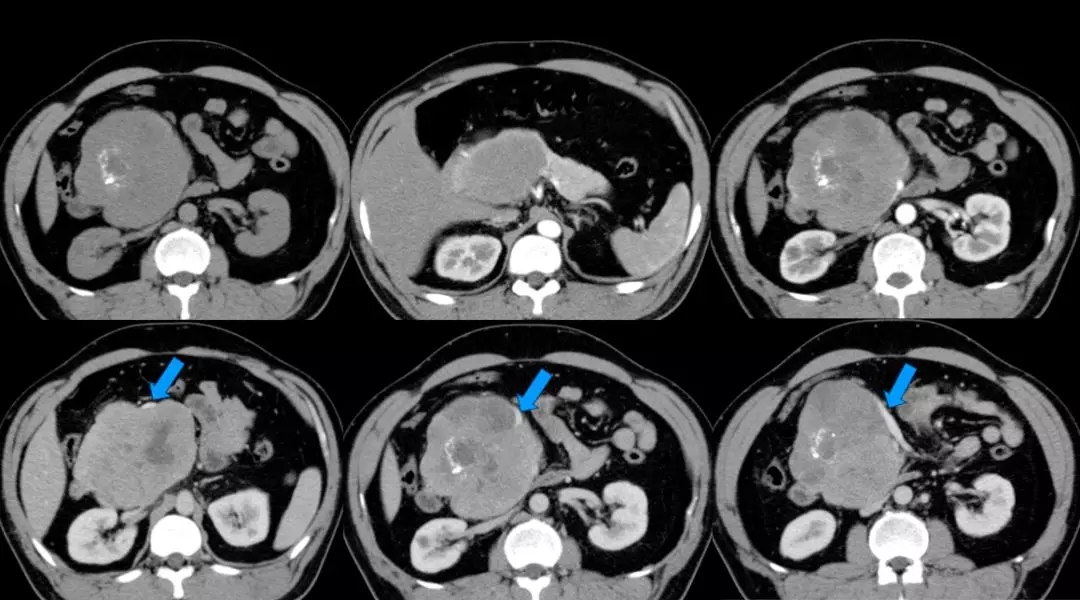

上腹部增强CT:胰头颈体积增大、胰头、颈部可见巨大软组织肿块影,长径约12 cm,与周围分界不清,其内密度不均匀,见片状低密度影及点片状致密影,增强扫描呈不均匀强化,病灶较胰腺实质强化幅度低,其内可见无强化坏死区。腹腔见数个小淋巴结影。脾周可见软组织密度影,长径约1.8 cm,强化方式与脾脏一致。双肾可见多个囊状无强化低密度影。左肺上叶可见斑片状密度增高影,增强可见明显强化。考虑:(1)胰头颈占位,考虑恶性;(2)副脾;(3)双肾多发囊状;(4)左上肺病变,炎症可能。(蓝色箭头为受侵PV-SMV)

术后上腹部增强CT血管重建显示门静脉通畅,肝脏血供良好